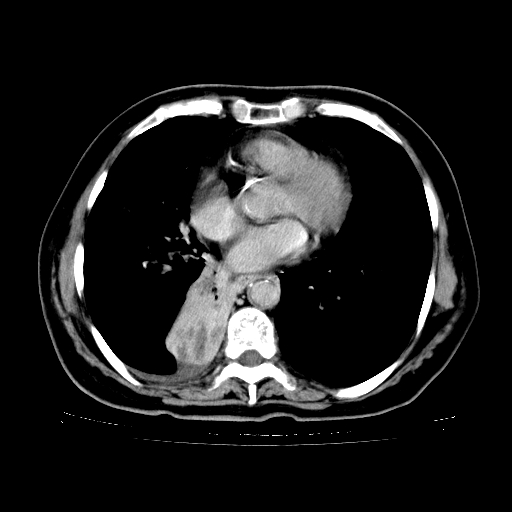

2.胸主动脉夹层。

4、主动脉夹层。

支持,首先一元论解释。胸主动脉部分层面环形低密度,中心强化。环形影不强化。不象真假腔的改变。我考虑动脉炎,不太支持夹层动脉瘤-和大家的观点不一致,希望楼主让患者再做个心血管的彩超吧。